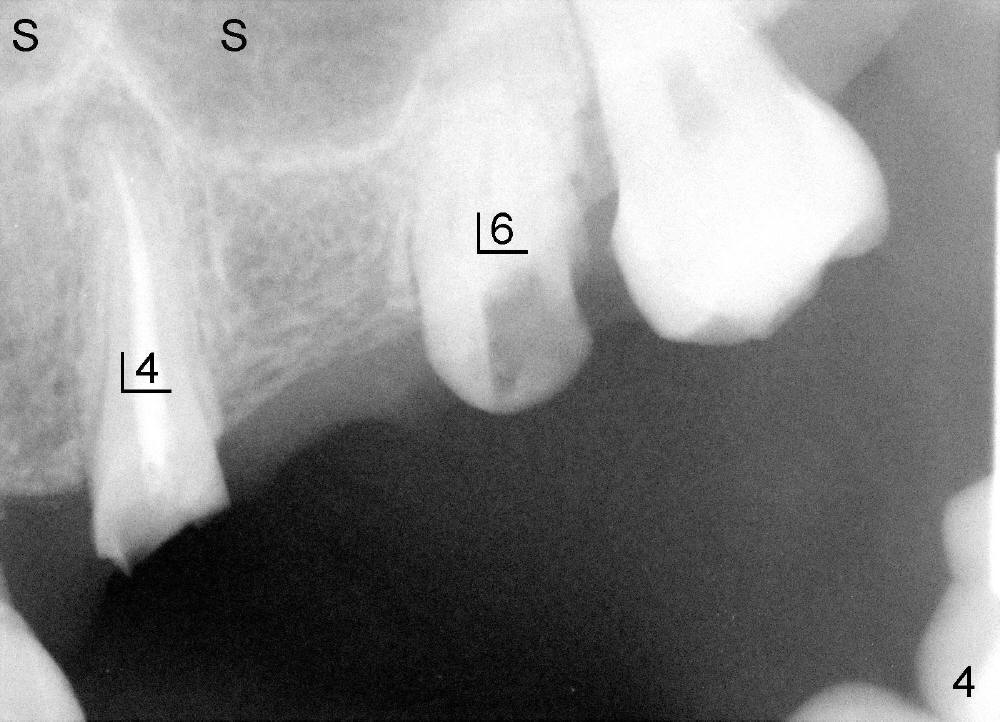

A 47-year-old lady has lost an upper left bridge (Fig.4,7). She is a dental phobic, but is concerned about cosmetics. Immediate implant and immediate provisional for the 1st bicuspid are easily accepted. There is a sinus septum above. Intraop PAs show that 4.5x17 mm tap (Fig.5) and 5x17 mm implant (Fig.6, insertion torque > 60 Ncm) are placed mesial to the septum without sinus membrane perforation. An abutment is placed immediately and an immediate provisional is fabricated.